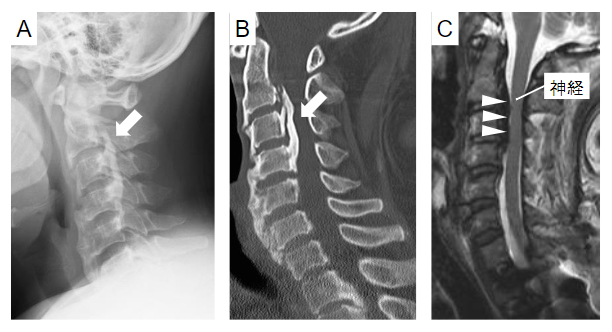

脊柱後縦靭帯骨化症(ossification of posterior longitudinal ligament:OPLL)は背骨に発生する疾患です(図1)。椎体後面を縦走する後縦靱帯が骨化することで背骨後方を走行する神経が圧迫され、重篤な運動・感覚障害が生じる難病です。50歳前後で発症することが多く、日本人を含む東アジア人に多いことが知られています。症状が重度な患者に対しては、神経の圧迫を取り除く手術が行われますが、根本的な治療方法はなく、予防法すら確立されていないのが現状です。

図1 脊柱後縦靭帯骨化症(OPLL)の画像所見

(A)頚部レントゲン、(B)CT、(C)MRIの矢状断像。脊柱後縦靱帯の骨化(白矢印)により、神経が前方から圧迫されている(白三角)。